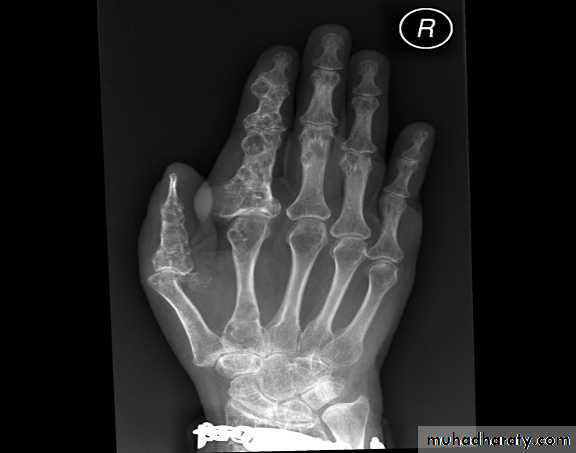

Multiple osteochondromasEnchondroma :

Site : small bones of the hands & feet

Clinical features : painless asymptomatic swelling.

Findings : lytic lesion with expansion & thinning of the cortex, no periosteal reaction unless pathological fracture develops.

1 % risk of malignant transformation in solitary type

Multiple enchondromatosis (Ollier's disease) affect long bones & carry 10% risk of malignant transformation.

Multiple chondromas in the hand